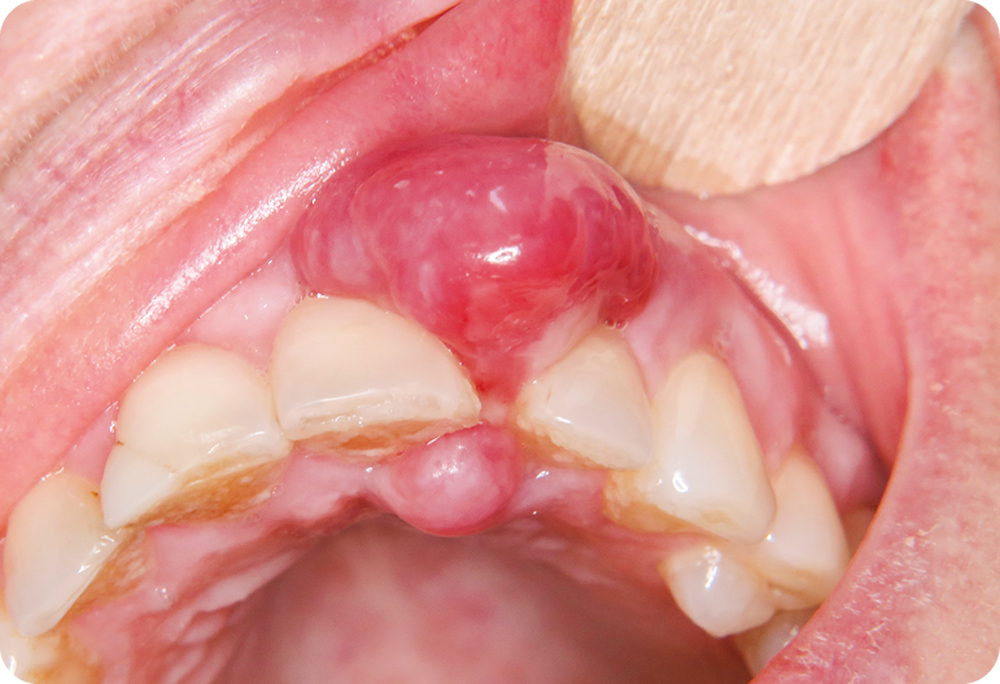

On observait un nodule gingival en bissac d’environ 1,5 cm de diamètre développé entre 21 et 22. Le nodule avait un aspect érythémateux violine et était par place ulcéré. La palpation révélait une lésion de consistance ferme. Le sondage objectivait une poche de 10 mm en vestibulaire de 22.